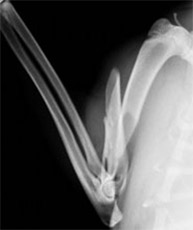

前肢橈尺骨骨折

1kg〜4kgの超小型犬が、室内でソファや抱っこの状態から飛び降りるくらいのことで骨折する場合が多いです。特に人気犬種のTプードルやチワワなどに多く認められます。

手術前

手術後

1.6kgのトイプードルの橈尺骨骨折です。プレートおよびスクリューを用いて固定、治療しました。